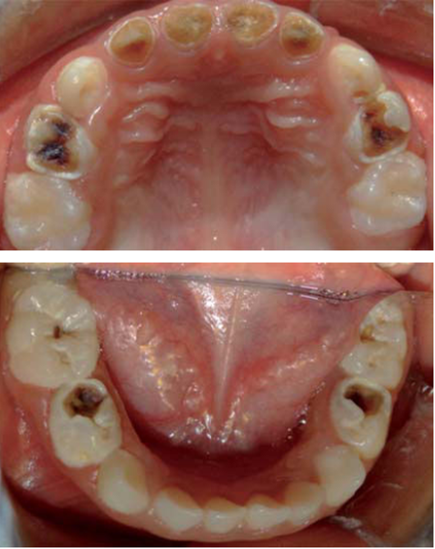

Se trata de paciente femenino de cinco años de edad proveniente de León, Guanajuato con diagnóstico de leucemia aguda linfoblástica precursora de células B, quien es referida a consulta odontológica por indicación del médico oncólogo tratante para rehabilitación dental urgente para poder comenzar el tratamiento con quimioterapia (Figura 2). Al revisar su historial médico se encuentra que la paciente debutó con palidez generalizada, debilidad, dolor óseo, petequias generalizas en la espalda, tórax y en las extremidades, al ser valorada por el médico pediatra es referida de inmediato al oncólogo por sospecha de leucemia. Debido a la nula cooperación de la paciente, a la complejidad de su padecimiento y a la urgencia del mismo se decide rehabilitar a la paciente bajo anestesia general (Figura 3).

Figura 2 Foto inicial de la paciente del presente caso quien fue diagnosticada con leucemia aguda linfoblástica B.

Figura 3 Condiciones iniciales de la cavidad bucal del paciente, motivo por el cual se decidió intervenir bajo anestesia general.